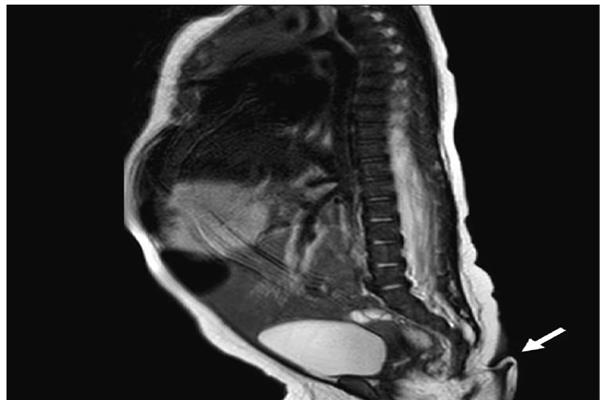

وفي غضون ذلك، عاين فريق الأطباء ذيل الفتاة، والذي كان طوله 5.7 سم وقطره بين 3 و5 ملم، كان هناك أيضًا شعر خفيف على الذيل وله طرف مدبب في نهايته.

وقال الأطباء إن الأم لم تكن تعاني من أي مشكلة أثناء الحمل. كما لم يكن هناك تاريخ سابق للإشعاع أو العدوى وما إلى ذلك. كما أن الأسرة لديها بالفعل ابن ولد بصحة جيدة. وفوجىء الأطباء أن الطفلة التي ولدت بذيل كانت تتمتع بصحة جيدة، حيث أظهرت اختبارات الدماغ والقلب والسمع والبول نتائج طبيعية. ولهذا قام الأطباء بإجراء أشعة سينية، للتحقيق من هذا الذيل، وكشفت عمليات المسح أن الذيل لم يكن نتيجة لمشكلة في العمود الفقري، كما لم يتم العثور على دليل على وجود عظام داخله.

و لم يكن الذيل متصلاً بالجهاز العصبي، مما يعني أنه يمكن إزالته جراحيًا. وأضاف الأطباء – كان الذيل ناعما مغطى بالجلد وعليه شعر فاتح، يمكن تحريكه دون التسبب في حدوث أي ألم للطفلة.